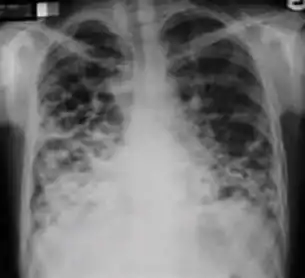

Chest x-ray showing patchy opacification on the upper right and mid-zone lung with fibrotic shadows, as well as bilateral hilar lymphadenopathy.

5. Hilar or mediastinal lymphadenopathy (bihilar lymphadenopathy) - Enlargement of lymph nodes in one or both hila or within the mediastinum, with or without associated atelectasis or consolidation.

Chest x-ray showing bilateral hilar adenopathy of primary pulmonary TB